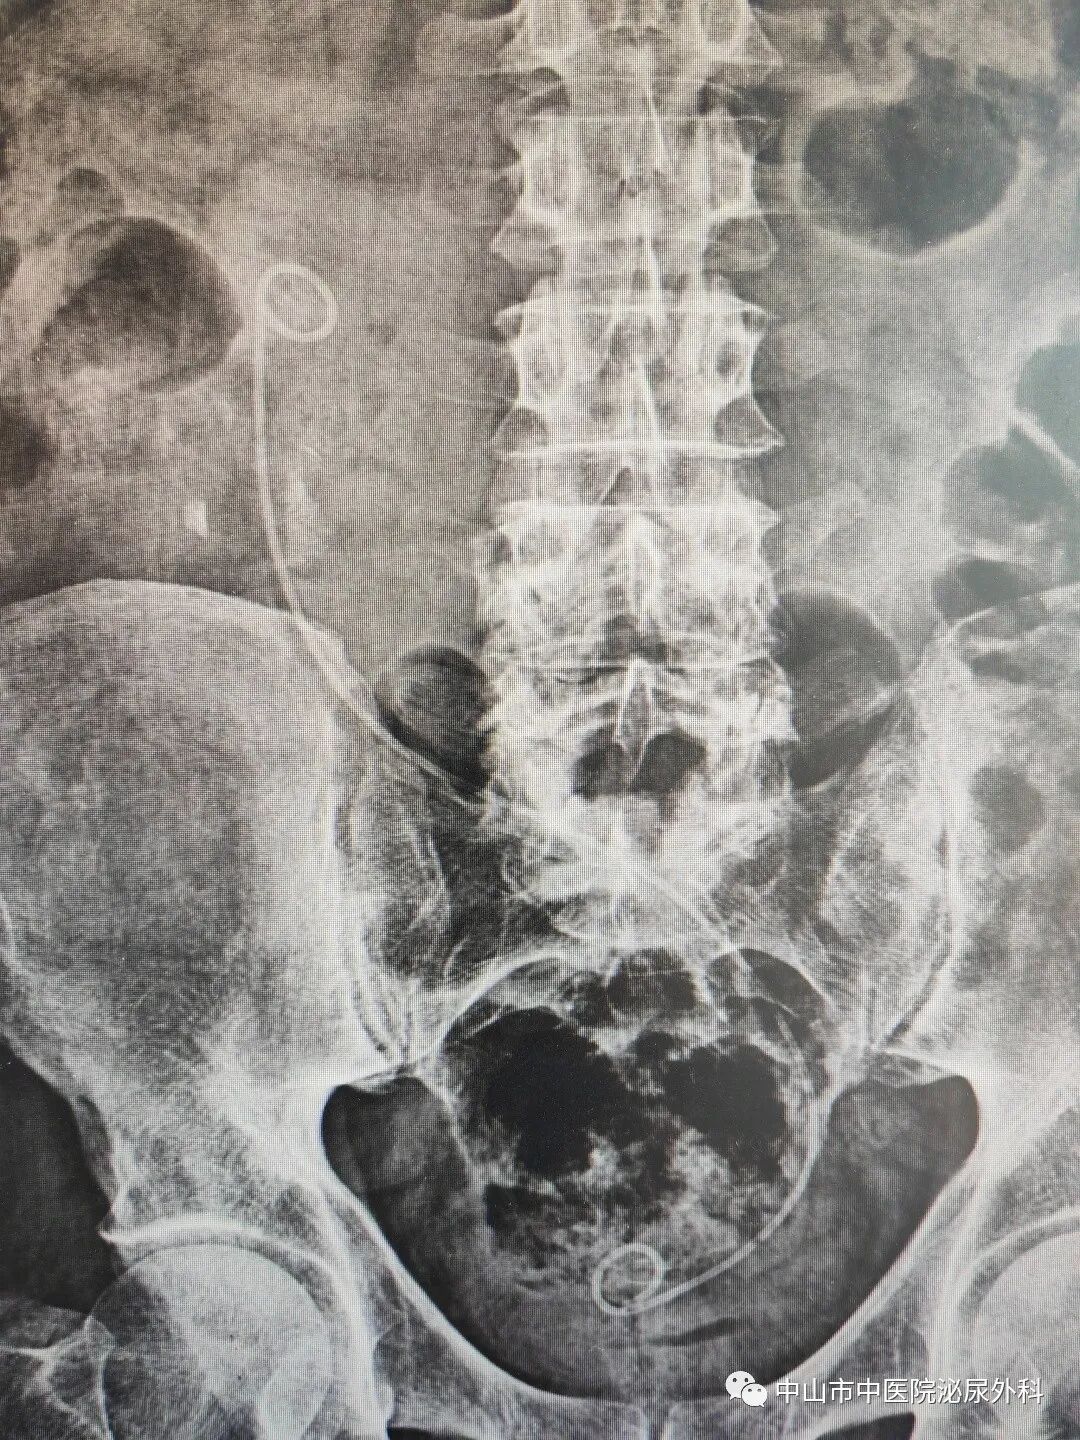

术前影像资料

输尿管鞘是什么一期软镜治疗罕见交叉异位肾并结石(术中使用一次性末端可弯负压清石鞘)_https://www.jmylbn.com_新闻资讯_第3张

输尿管鞘是什么一期软镜治疗罕见交叉异位肾并结石(术中使用一次性末端可弯负压清石鞘)_https://www.jmylbn.com_新闻资讯_第4张